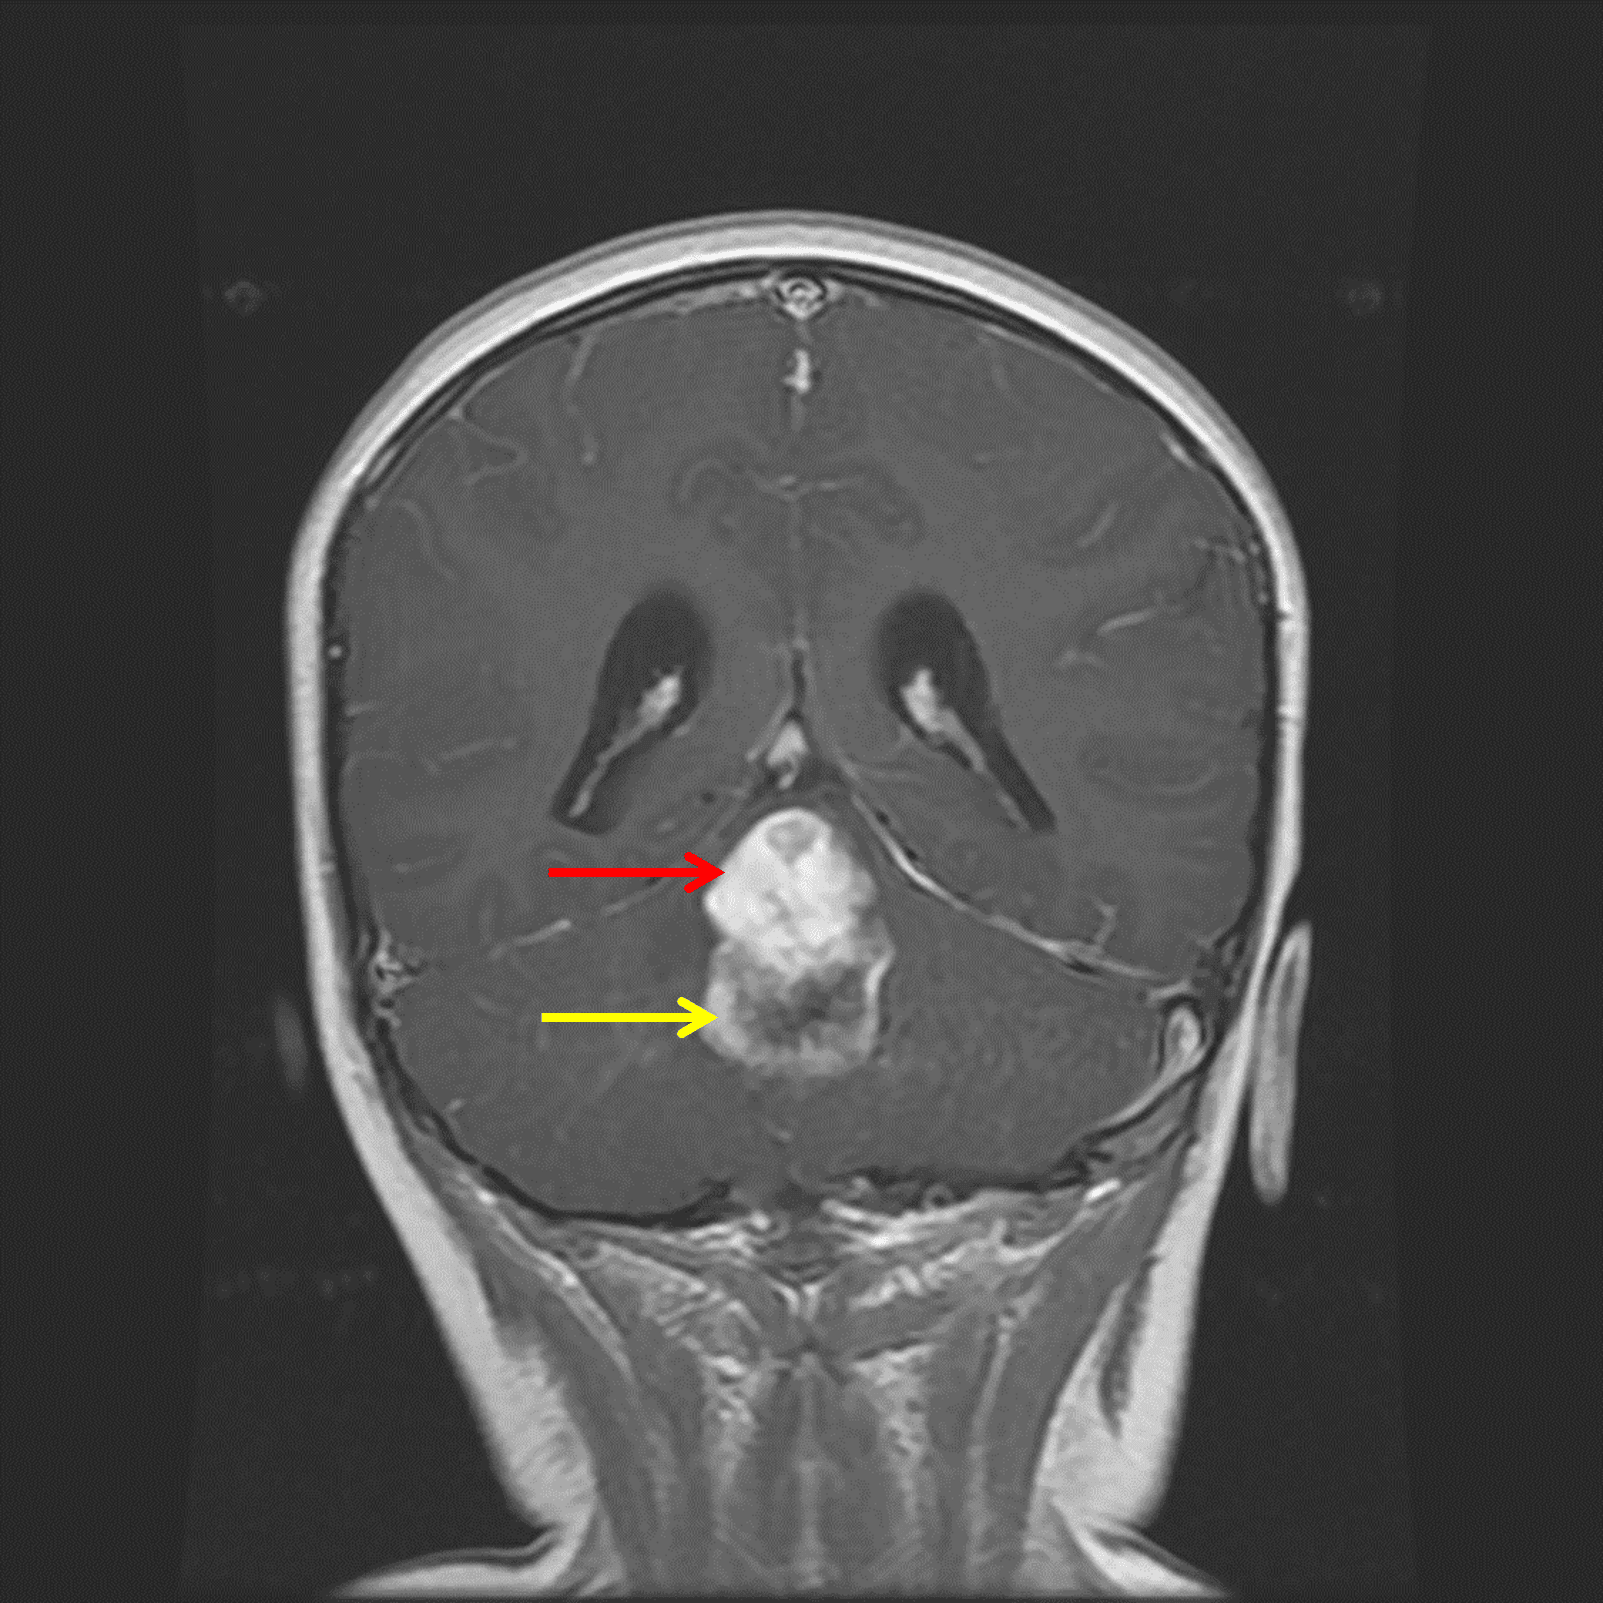

Midline posterior fossa mass with a superior solid component (red arrow) and inferior peripherally-enhancing cystic component (yellow arrow).